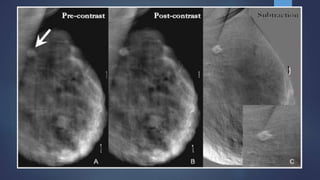

 1. Temporal Subtraction :

 Done by acquisition of high-energy images before and after contrast medium

injection.

 The temporal subtraction technique offers the possibility to analyze the

kinetic curve of enhancement of breast lesions.

 Dual-energy takes advantage of the difference in the atomic density of

tissue, as compared to the contrast. Two images are acquired, and the low-

density breast tissue is subtracted; however, the high energy of contrast

persists, allowing any enhancing abnormality to be more visible.

 The main disadvantages of this technique are that only a single breast can be

imaged and patients have to maintain a particular position (usually MLO) for

a prolonged period

 Prone to Motion artifacts

Post-contrast images show an enhancing

lesion infero-medial quadrant - DCC

Post contrast images show an enhancing

lesion proved to be malignant on biopsy